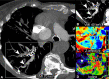

CT systems equipped with photon-counting detectors (PCDs), referred to as photon-counting CT (PCCT), are beginning to change imaging in several subspecialties, such as cardiac, vascular, thoracic, and musculoskeletal radiology. Evidence has been building in the literature underpinning the many advantages of PCCT for different clinical applications. These benefits derive from the distinct features of PCDs, which are made of semiconductor materials capable of converting photons directly into electric signal. PCCT advancements include, among the most important, improved spatial resolution, noise reduction, and spectral properties. PCCT spatial resolution on the order of 0.25 mm allows for the improved visualization of small structures (eg, small vessels, arterial walls, distal bronchi, and bone trabeculations) and their pathologies, as well as the identification of previously undetectable anomalies. In addition, blooming artifacts from calcifications, stents, and other dense structures are reduced. The benefits of the spectral capabilities of PCCT are broad and include reducing radiation and contrast material dose for patients. In addition, multiple types of information can be extracted from a single data set (ie, multiparametric imaging), including quantitative data often regarded as surrogates of functional information (eg, lung perfusion). PCCT also allows for a novel type of CT imaging, K-edge imaging. This technique, combined with new contrast materials specifically designed for this modality, opens the door to new applications for imaging in the future.